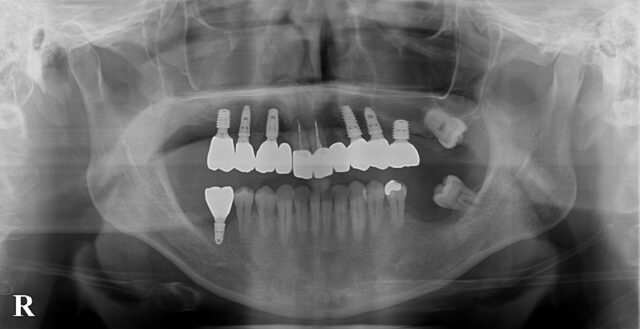

AFTER

術後